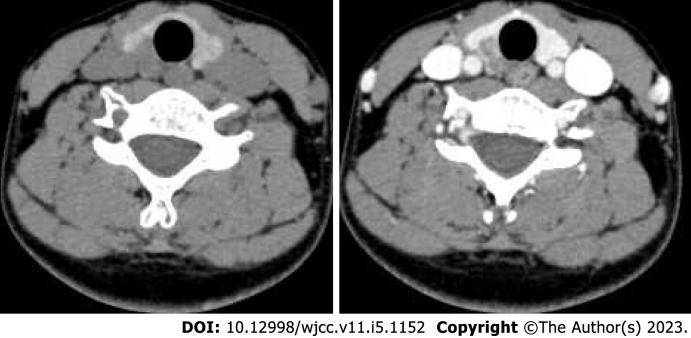

误诊为甲状腺恶性肿瘤的朗格汉斯细胞组织细胞增多症:一例报告。

Langerhans cell histiocytosis misdiagnosed as thyroid malignancy: A case report.

CASE SUMMARY

We report a young woman with a thyroid nodule. Thyroid malignancy was suggested by fine needle aspiration, but she was eventually diagnosed with multisystem LCH, thus avoiding thyroidectomy.

病例摘要

我们报告一名患有甲状腺结节的年轻女性。细针穿刺提示甲状腺恶性肿瘤,但她最终被诊断为多系统LCH,从而避免了甲状腺切除术。